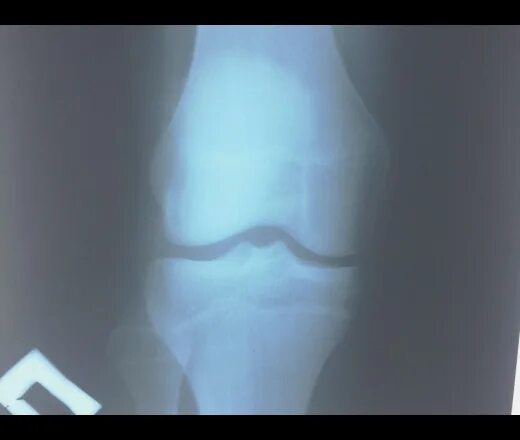

Болезнь осгуда мкб